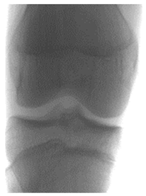

3.1. Dataset Description